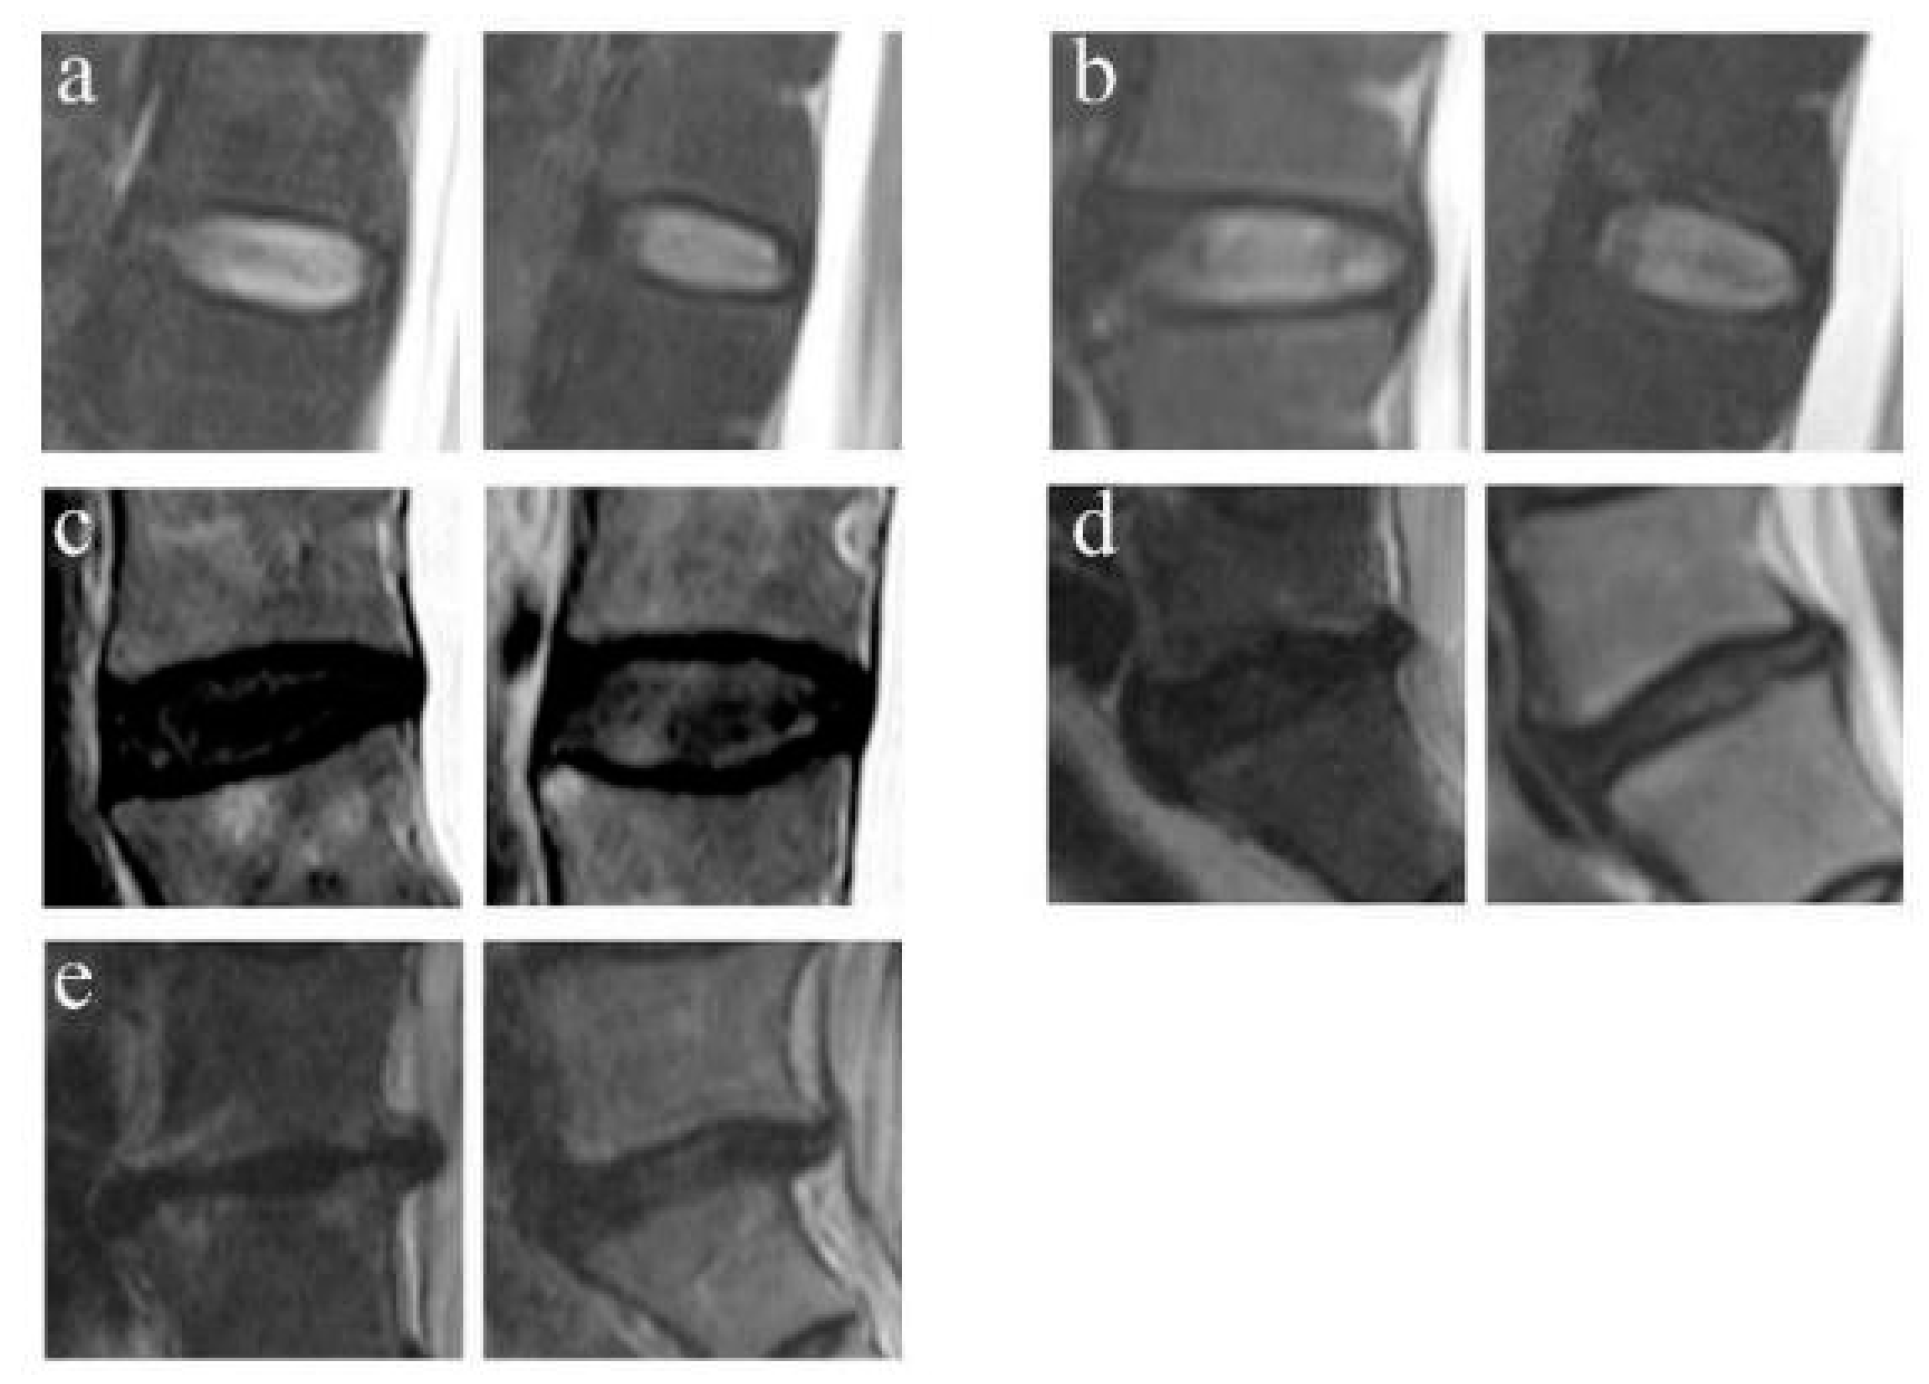

2.4.2. Disc Degeneration Grading

4.4. Facet Joint Osteoarthritis